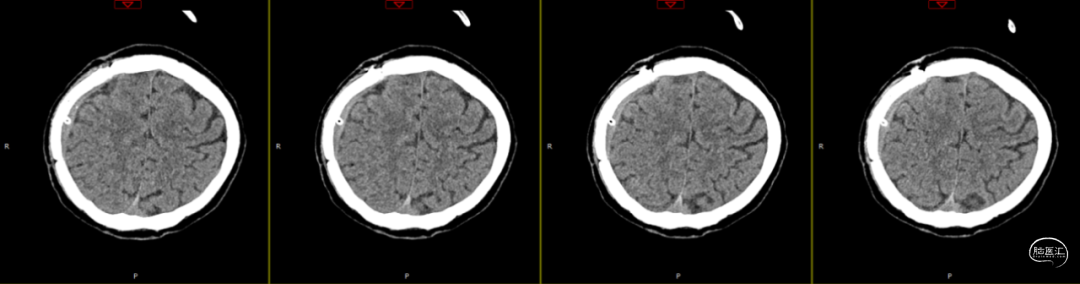

因患者局部头皮逐渐膨隆,且头皮疼痛,于术后89天再次入院。体查可触及头皮下异常物质存在,考虑头皮下积脓并硬膜外脓肿可能,患者无发热,血常规、C反应蛋白、降钙素原等感染指标均为在正常范围。

第1次术后88天,即第2次入院前1天复查(如上图),经反复沟通病情,病人及家属仍拒绝去除骨瓣清创手术,但同意进行手术清创。术中见右侧额部皮下炎性肉芽组织增生,伴有少量分泌物流出,骨瓣下见乳白色脓性分泌物,未闻及明显异味,收集脓性液体送细菌培养、涂片检查,局部硬膜增厚,较多炎性增生组织于局部硬脑膜黏连紧密,缓慢刮除局部异常增生组织后,低功率双极电凝行硬脑膜止血,骨瓣可见右侧额部外板局部被侵蚀,清理表面异物后,使用双氧水浸泡冲洗,并浸入碘伏液中消毒;彻底清除硬膜外、骨缘及右侧额部皮下增生异常组织,额顶部愈合不良刀口予以局部清创,反复使用双氧水及稀释后碘伏溶液冲洗创面,更换钛板及钛钉,还纳骨瓣并固定,皮下留置负压引流管1根,缝合逐层。术后使用万古霉素静脉抗炎治疗,留取术中脓性分泌物进行细菌培养及涂片检查(培养及检验均呈阴性)。

第2次术后第1天复查颅脑CT资料(第1次术后92天)(如上图)。